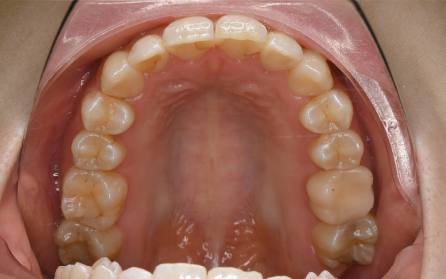

19歳 女性

主訴 「前歯のでこぼこを治したい」

診断 「両側側切歯のクロスバイトを伴う叢生症例」

上下前歯部の叢生の改善のため、歯と歯の間を0.5mm程度削ってスペースを確保しながら歯を並べました。患者さんの協力(マウスピースの使用状況等)も良好で、前歯が前方に突出することなく側切歯(2番目の歯)のクロスバイトも改善されました。前歯が突出しないように治療計画をたてないと口唇が閉じにくくなったり、口元がもっこりしてしまいます。治療期間は18か月でしたが、動的治療後は歯を安定させるために保定装置の使用が必要です(最低2年)。矯正治療では患者さんの協力が非常に重要であり(特にマウスピース矯正の場合は使用時間)、治療結果や治療期間に影響します。また、歯の移動にはワイヤー矯正、マウスピース矯正にかかわらず歯根吸収、歯肉退縮、歯髄壊死のリスクがあります。